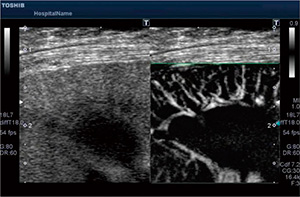

図2 従来の手法とSMIによる血流イメージングの比較

SMIは,造影剤が適用されない場合でも,低流速検出能に優れた血流イメージングを提供することが可能である。がんや腫瘍,関節リウマチなどの早期診断や治療方針の決定などをサポートし,さらに造影剤を使うことで,より感度の良い確かな診断に貢献することが期待されている(図3,4)。

図3 SMIによる肝臓の描出 |

図4 SMIによる腎臓の描出 |